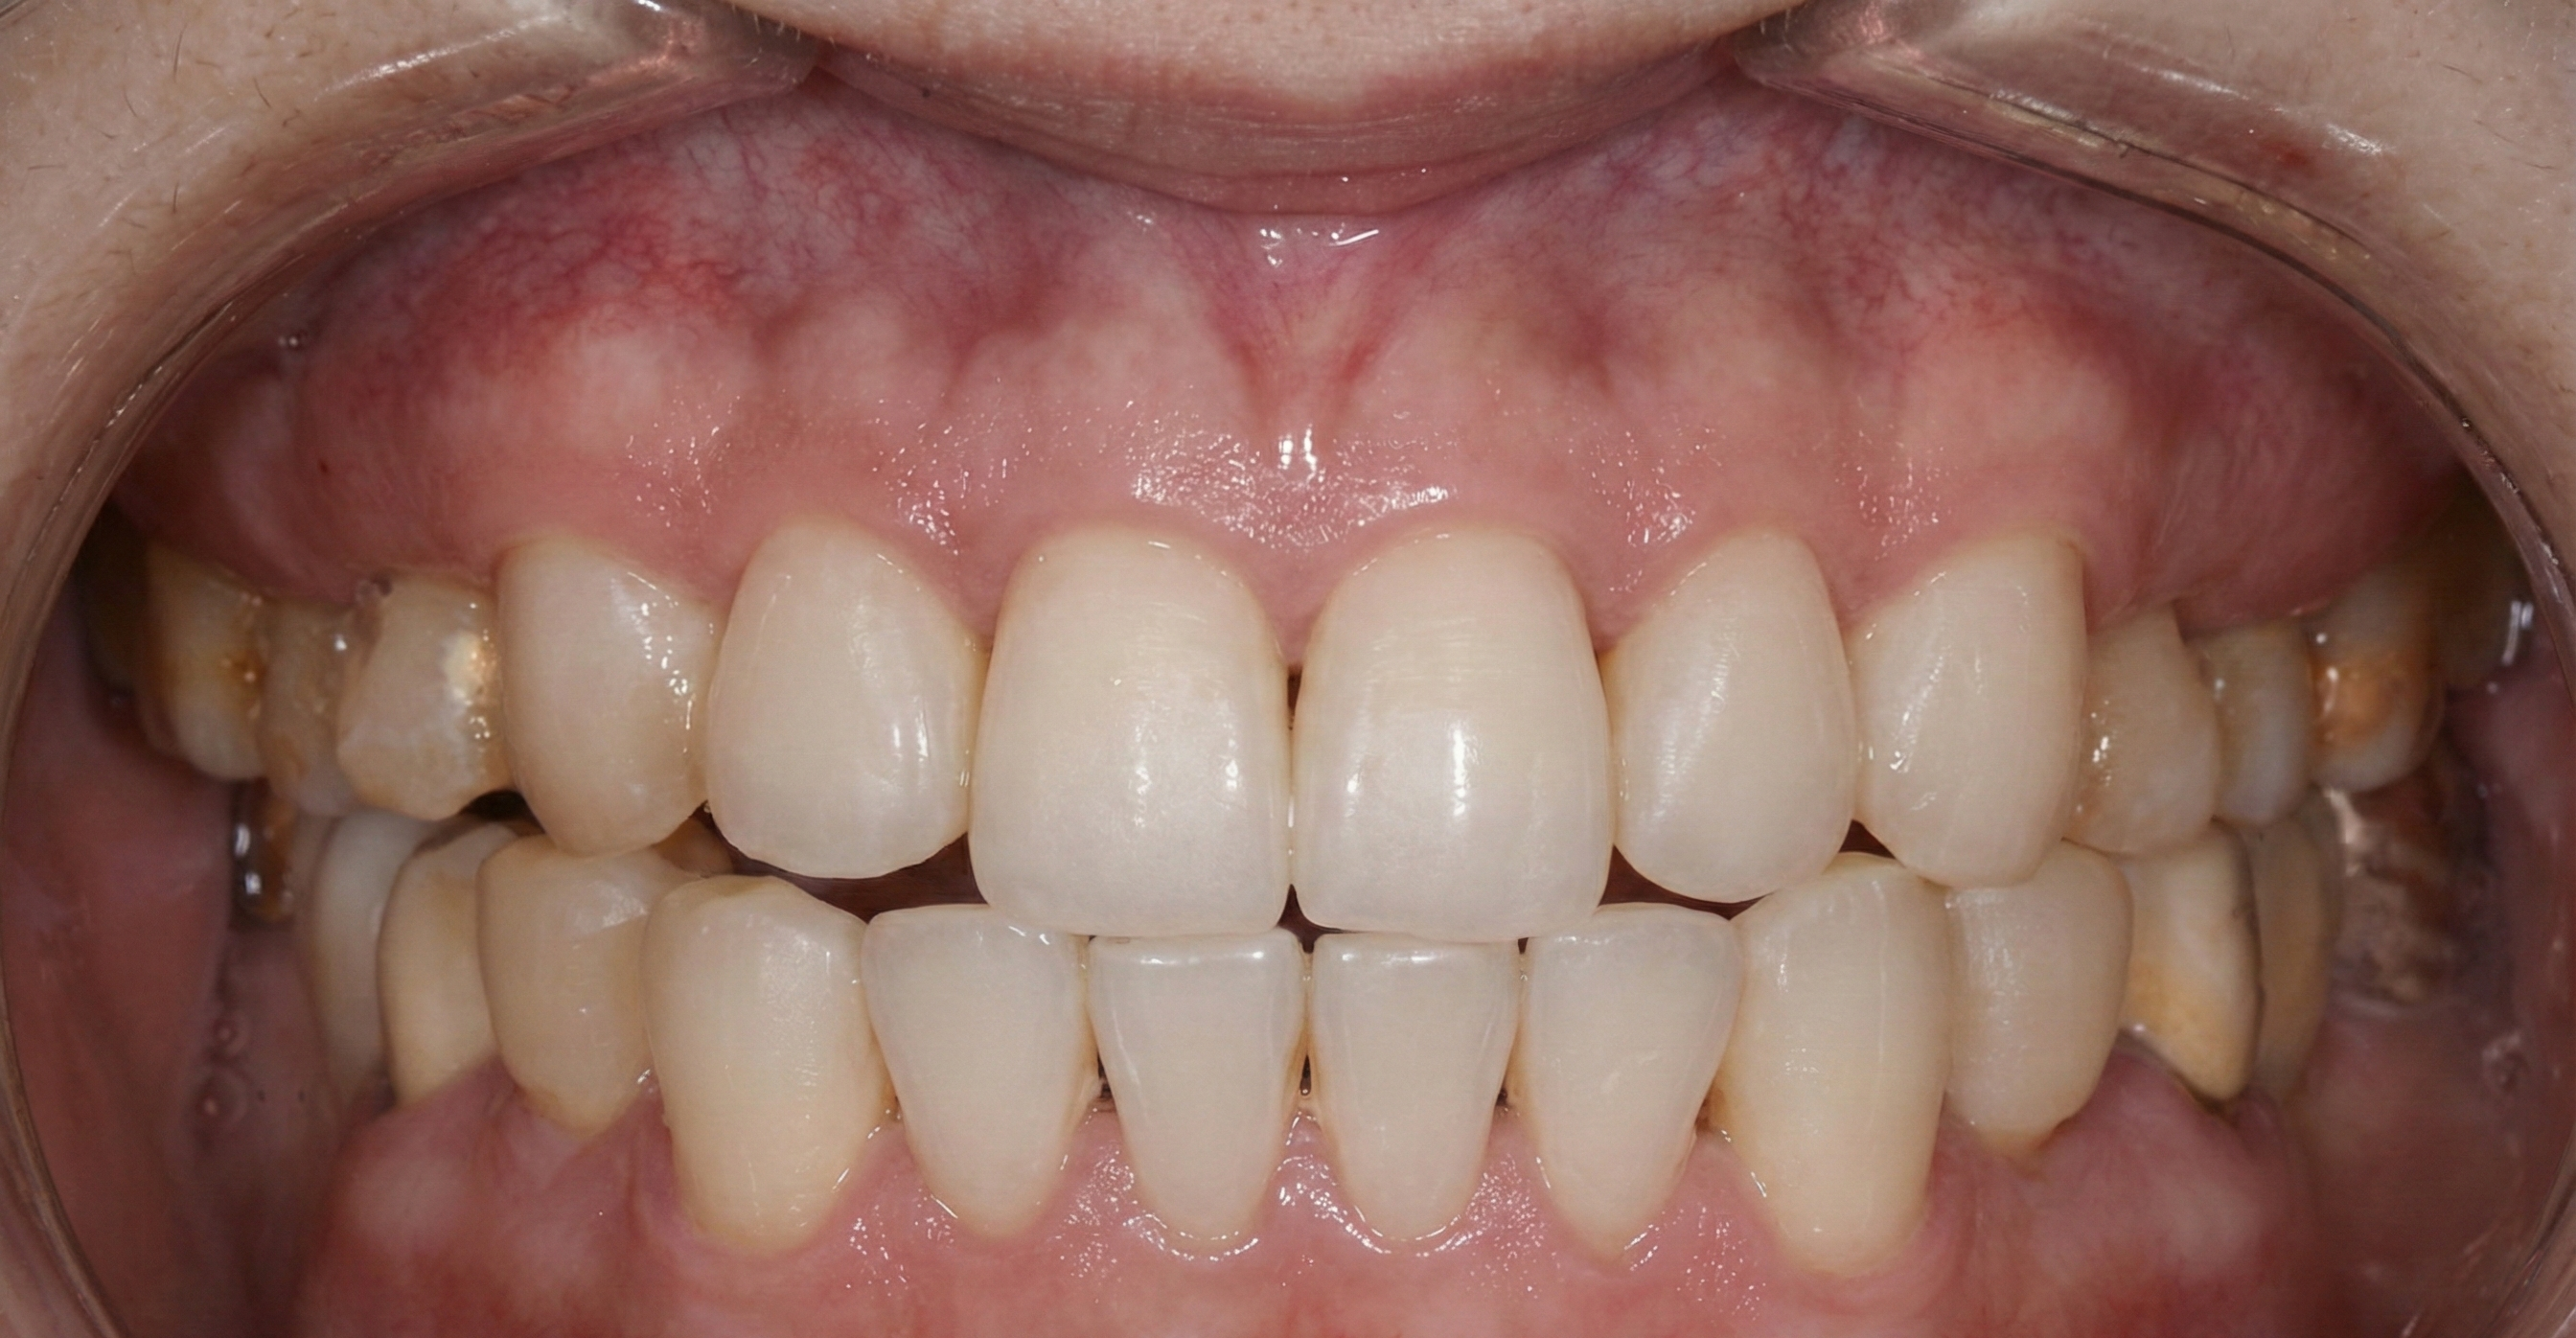

Generalized Recession

Challenge: Generalized recession exposing root surfaces, leading to dentinal hypersensitivity and esthetic compromise.

Solution: Pinhole® Surgical Technique (PST). A minimally invasive, scalpel-free, and suture-free procedure to advance tissue.

Outcome: 100% root coverage achieved generalized. Stable, thick keratinized tissue band with immediate cosmetic improvement.